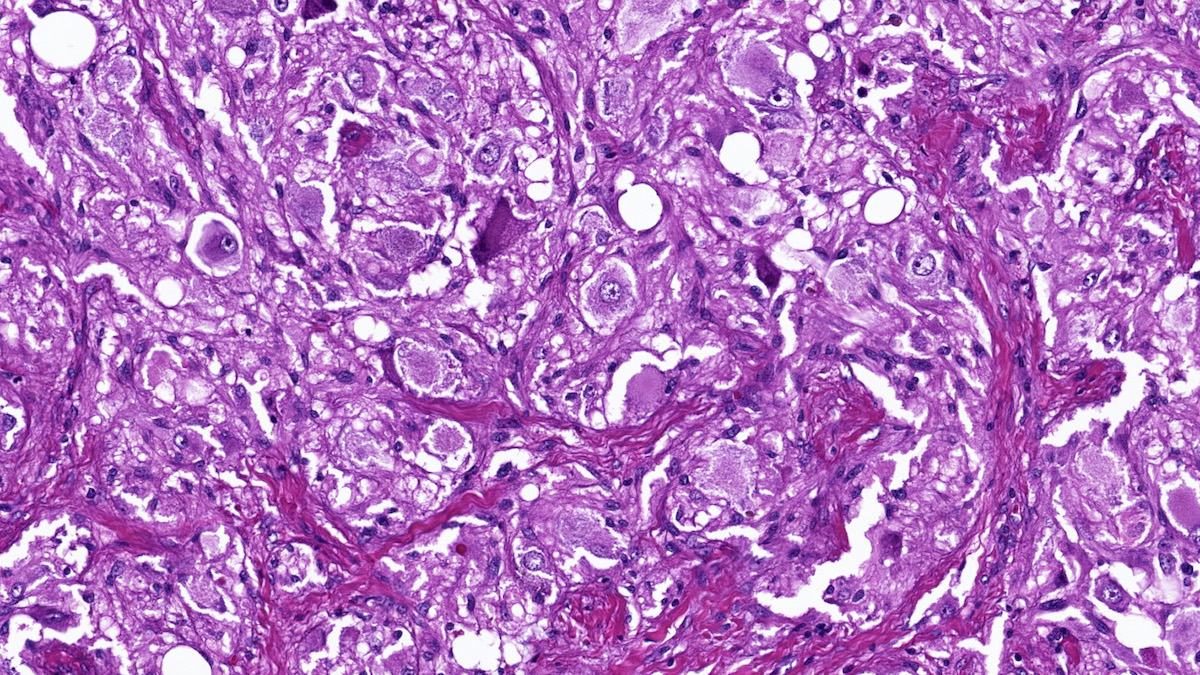

Microscopic (histologic) description

- Prevailing histologic pattern: epithelioid chief cells arranged in distinctive clusters / nests (zellballen pattern), separated by prominent fibrovascular stroma (J Clin Med 2018;7:280)

- Other patterns: pseudorosette, angioma-like, spindled and sclerosing

- Chief cells: round, oval to polygonal cells with abundant granular basophilic, eosinophilic or amphophilic cytoplasm (Surg Pathol Clin 2019;12:951)

- Intracytoplasmic hyaline globules may be present in sympathoadrenal paragangliomas

- May have dysmorphic vessels, melanin-like pigment (neuromelanin) (pigmented paraganglioma), amyloid, abundant stroma and osseous metaplasia (Diagn Pathol 2012;7:77, Hum Pathol 1992;23:33)

- VHL syndrome: prominent stromal edema, clear cytoplasm and lipid degeneration (Am J Surg Pathol 1987;11:480)

Microscopic (histologic) images

Contributed by Luvy Delfin, M.D. and Sylvia L. Asa, M.D., Ph.D.